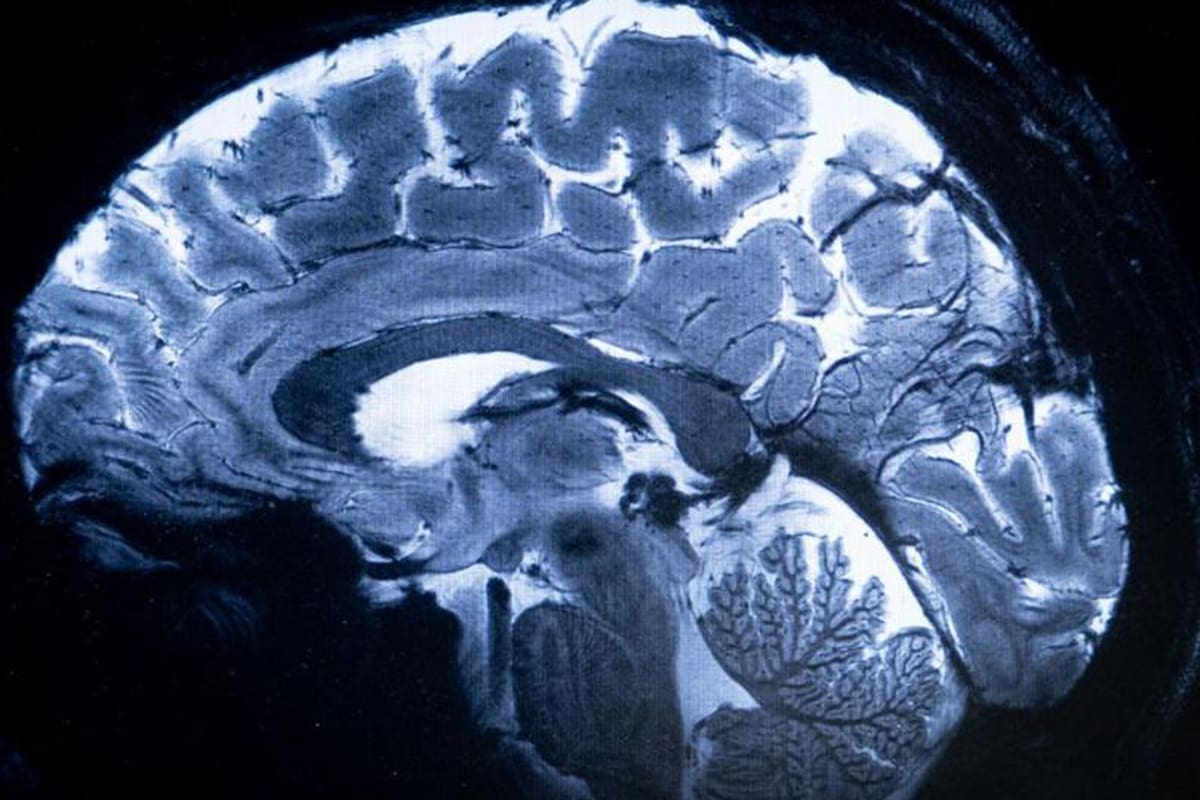

Para averiguarlo, los científicos realizaron resonancias magnéticas a 3.226 personas, mujeres (53 %) y hombres (47 %) de entre 45 y 74 años. Comparando las imágenes de los voluntarios nacidos entre las décadas de 1930 y 1970, encontraron que, en promedio, los cerebros de los participantes de los 70 presentaban un volumen un 6,6 % más grande que los de los sujetos venidos al mundo cuarenta años antes, sin diferencias significativas entre hombres y mujeres.

El crecimiento afectaría a áreas importantes como la sustancia blanca –red de axones mielinizados que permiten la comunicación entre las distintas áreas dentro y fuera del sistema nervioso–, la sustancia gris cortical –donde se llevan a cabo la mayoría de los procesos cognitivos y emocionales– y el hipocampo, estructura responsable de diversas funciones cognitivas como la memoria o la capacidad para orientarse y desplazarse.